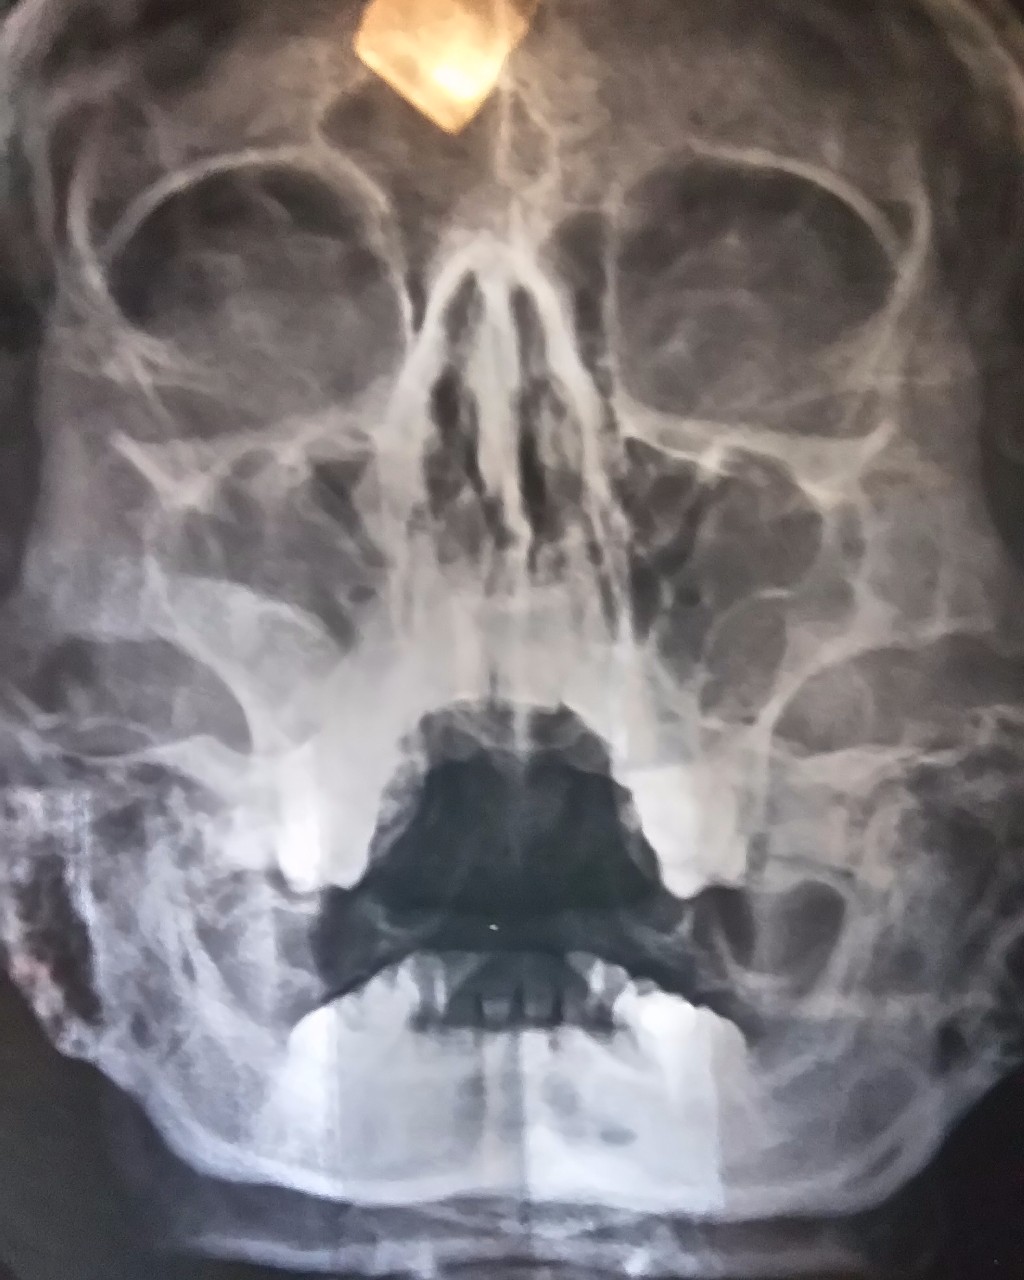

ΠΠ’ ΠΠΠ. ΠΠΎΠ»ΠΈΠΏΠΎΠ·Π½ΡΠΉ ΠΏΠ°Π½ΡΠΈΠ½ΡΡΠΈΡ. ΠΡΠ΅ΠΊ ΡΠ»ΠΈΠ·ΠΈΡΡΠΎΠΉ ΠΎΠ±ΠΎΠ»ΠΎΡΠΊΠΈ Π²Π΅ΡΡ

Π½Π΅ΡΠ΅Π»ΡΡΡΠ½ΡΡ

ΠΏΠ°Π·ΡΡ

(ΠΊΡΠ°ΡΠ½Π°Ρ ΡΡΡΠ΅Π»ΠΊΠ°), ΠΏΠΎΠ»ΠΈΠΏΠΎΠ²ΠΈΠ΄Π½ΡΠ΅ ΠΎΠ±ΡΠ°Π·ΠΎΠ²Π°Π½ΠΈΡ Π² Π²/ΡΠ΅Π»ΡΡΡΠ½ΡΡ

Π°Ρ

(ΡΠΈΠ½ΡΡ ΡΡΡΠ΅Π»ΠΊΠ°), Π²ΡΡΠ°ΠΆΠ΅Π½Π½ΠΎΠ΅ ΡΠ½ΠΈΠΆΠ΅Π½ΠΈΠ΅ ΠΏΠ½Π΅Π²ΠΌΠ°ΡΠΈΠ·Π°ΡΠΈΠΈ ΠΏΠΎΠ»ΠΎΡΡΠΈ Π½ΠΎΡΠ° (Π·Π΅Π»Π΅Π½Π°Ρ ΡΡΡΠ΅Π»ΠΊΠ°).

ΠΠ’ ΠΠΠ. ΠΠΎΠ»ΠΈΠΏΠΎΠ·Π½ΡΠΉ ΠΏΠ°Π½ΡΠΈΠ½ΡΡΠΈΡ. ΠΡΠ΅ΠΊ ΡΠ»ΠΈΠ·ΠΈΡΡΠΎΠΉ ΠΎΠ±ΠΎΠ»ΠΎΡΠΊΠΈ Π²Π΅ΡΡ Π½Π΅ΡΠ΅Π»ΡΡΡΠ½ΡΡ ΠΏΠ°Π·ΡΡ (ΠΊΡΠ°ΡΠ½Π°Ρ ΡΡΡΠ΅Π»ΠΊΠ°), ΠΏΠΎΠ»ΠΈΠΏΠΎΠ²ΠΈΠ΄Π½ΡΠ΅ ΠΎΠ±ΡΠ°Π·ΠΎΠ²Π°Π½ΠΈΡ Π² Π²/ΡΠ΅Π»ΡΡΡΠ½ΡΡ ΠΏΠ°Π·ΡΡ Π°Ρ (ΡΠΈΠ½ΡΡ ΡΡΡΠ΅Π»ΠΊΠ°), Π²ΡΡΠ°ΠΆΠ΅Π½Π½ΠΎΠ΅ ΡΠ½ΠΈΠΆΠ΅Π½ΠΈΠ΅ ΠΏΠ½Π΅Π²ΠΌΠ°ΡΠΈΠ·Π°ΡΠΈΠΈ ΠΏΠΎΠ»ΠΎΡΡΠΈ Π½ΠΎΡΠ° (Π·Π΅Π»Π΅Π½Π°Ρ ΡΡΡΠ΅Π»ΠΊΠ°).